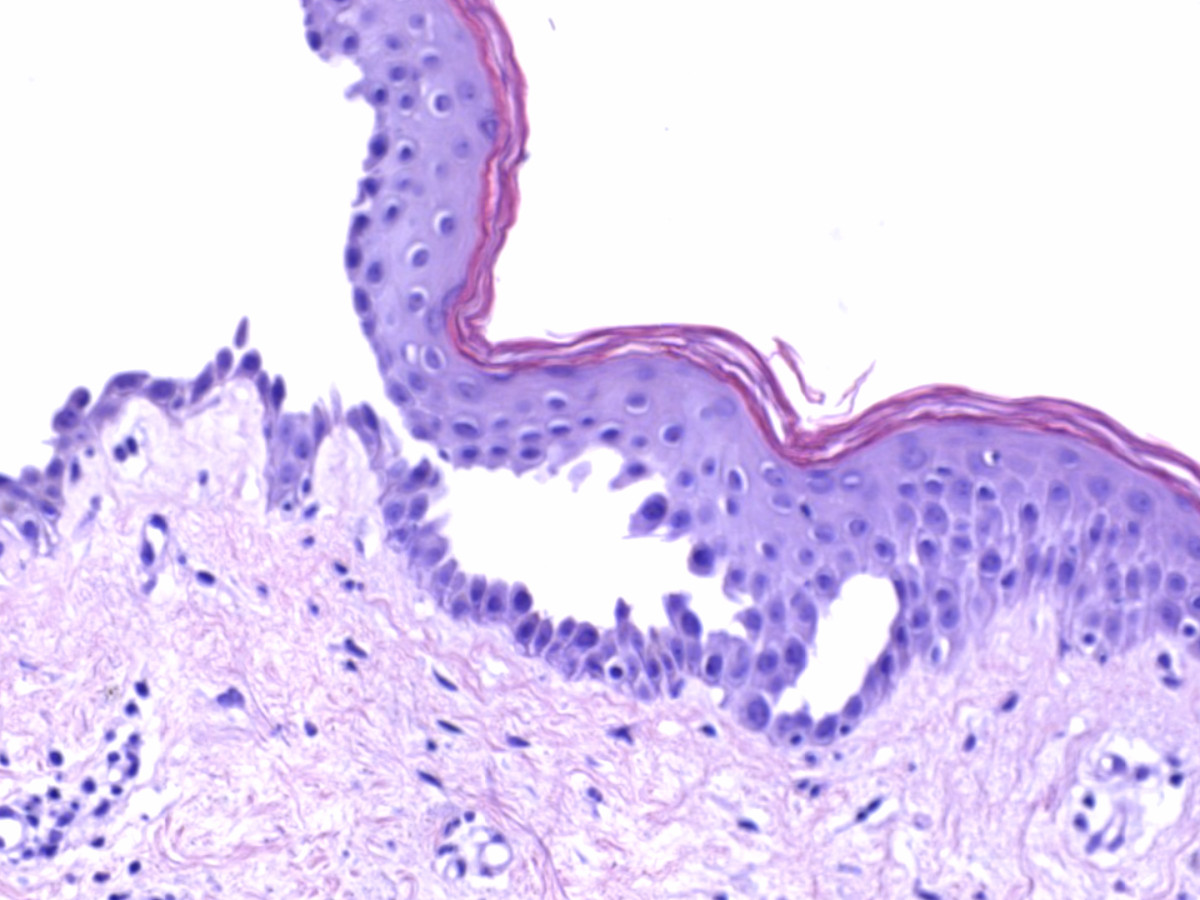

Aanvullend onderzoek:

Histologie (biopt met daarin een randje van de blaar voor

HE, de IF uit de normale peri-lesionale huid); vroeg stadium: spongiotische

dermatitis met oedeem vooral laag in de epidermis. Later suprabasale acantholyse

met vorming van intra-epidermale splijting en blaren, ook in de follikels. Basale

cellen splijten van elkaar, niet van de basale laag waardoor de basale keratinocyten

een 'thombstone' (grafstenen) aspect hebben. De blaarholte bevat acantholytische

keratinocyten, fibrine, en eosinofiele granulocyten. Geen / weinig dyskeratotische

cellen. Dermis: superficieel gemengdcellig perivasculair en interstitieel infiltraat

met veel eosinofiele granulocyten.